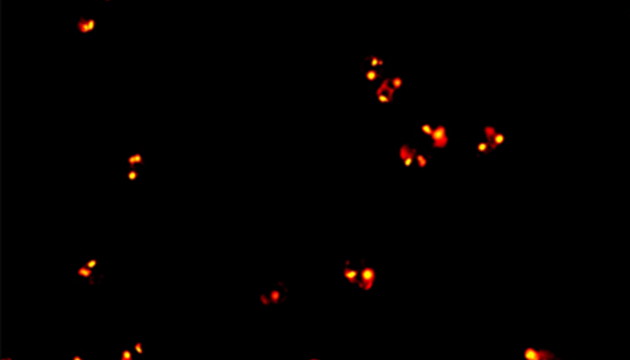

CTC檢測(cè)用于上皮腫瘤,如胃腸癌、皮膚癌等。檢測(cè)分四步:富集、CD45染白細(xì)胞、CK染CTC、DAPI染核。有DAPI、CK熒光且無(wú)CD45熒光,大核細(xì)胞為CTC;有DAPI、CD45熒光為白細(xì)胞。

CTC檢測(cè)面臨儀器通用性差、多色熒光閱片繁瑣及高靈敏度成像難三大難點(diǎn)。新技術(shù)如微流控芯片有望取代專(zhuān)用儀器,提升富集效率。使用電動(dòng)熒光顯微鏡搭配微流控,可更高效率進(jìn)行CTC成像和閱片。另外為滿(mǎn)足高靈敏度成像需求,建議配置優(yōu)質(zhì)LED光源、高效濾光片、半復(fù)消色差或以上物鏡及高靈敏度相機(jī)。

MF43-N用于CTC檢測(cè)